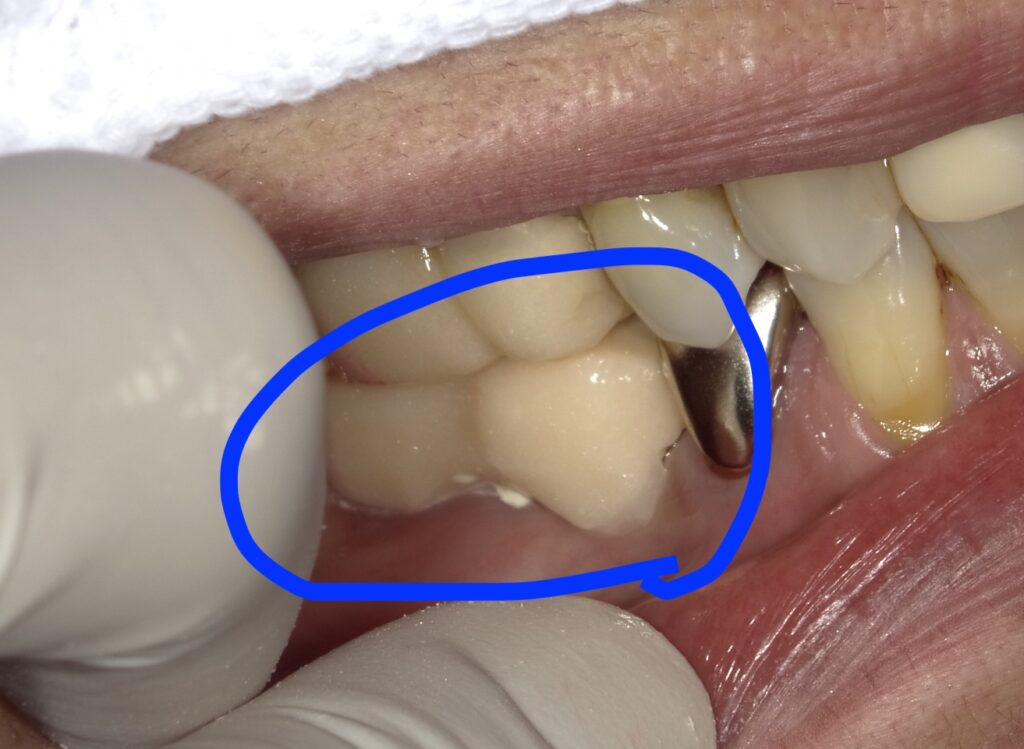

○で囲ったのが仮歯です。プラスチックですので

かけやすくまた変色しやすいです。